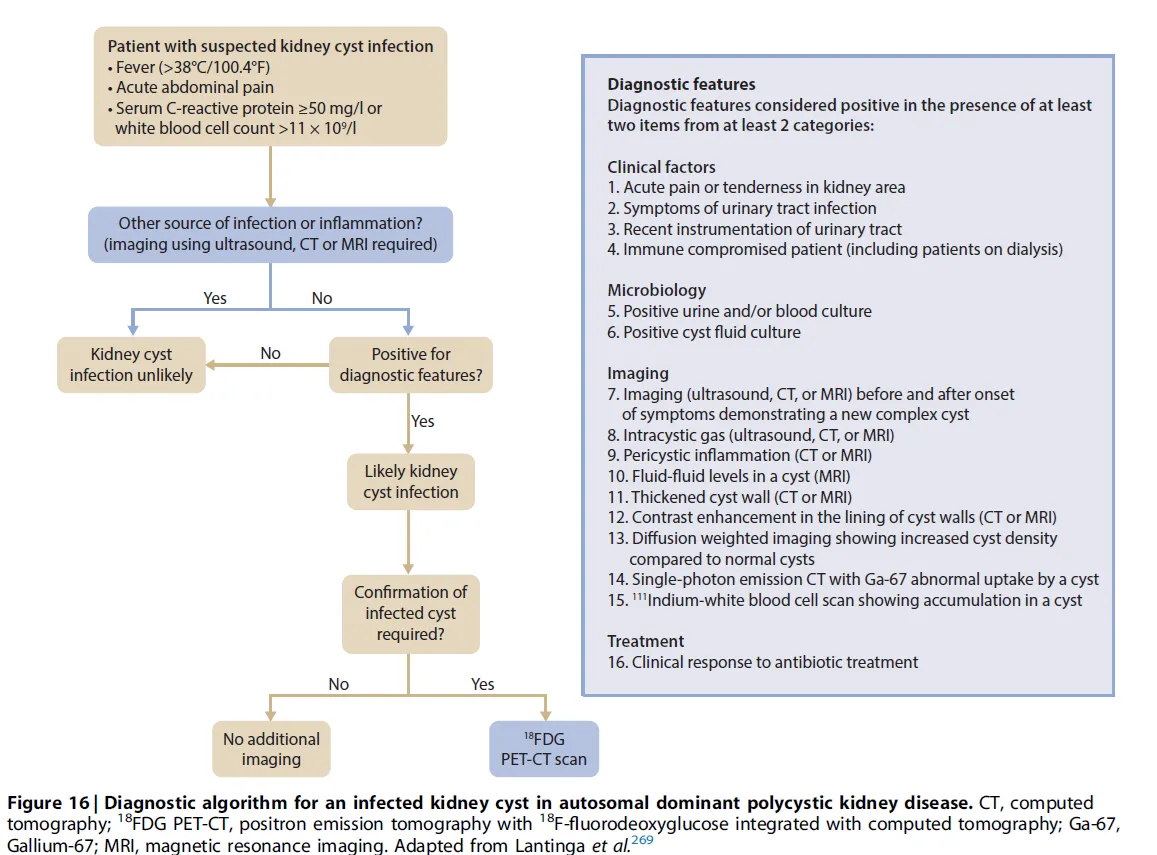

O novo fluxograma da KDIGO 2025 (**[link](https://kdigo.org/wp-content/uploads/2025/01/KDIGO-2025-ADPKD-Guideline.pdf)**) ajuda a estruturar o diagnóstico e a condução desses casos, reconhecendo que, muitas vezes, os achados clínicos e de imagem se sobrepõem a outras causas de dor ou febre.

Pacientes com DRPAD que apresentam febre, dor abdominal ou lombar aguda, elevação de leucócitos e/ou PCR devem ser investigados para infecção de cistos renais.

A presença de dor à palpação renal, piúria ou uro/bacteremia positiva reforça a suspeita clínica.

**🔍 Como investigar:**

TC ou RM com contraste podem identificar novo cisto complexo, mas geralmente não diferenciam sangue de pus no interior do cisto.

Achados como realce de parede, espessamento, gás intralesional ou alterações inflamatórias pericísticas aumentam a probabilidade de infecção.

Punção aspirativa pode ser considerada para confirmação diagnóstica e cultura dirigida.

💡 E quando o diagnóstico permanece incerto?

O 18F-FDG PET/CT surge como ferramenta de maior especificidade, útil para localizar o(s) cisto(s) infectado(s) e definir o alvo da punção.

Entretanto, a KDIGO ressalta que o PET/CT não deve ser exame de rotina, devendo ser reservado para casos selecionados, quando os métodos convencionais não esclarecem o diagnóstico.

🧠 O fluxograma da KDIGO 2025 reflete consenso internacional de especialistas em doenças renais e hepáticas policísticas, destacando as características de imagem mais úteis para diferenciação e tomada de decisão.